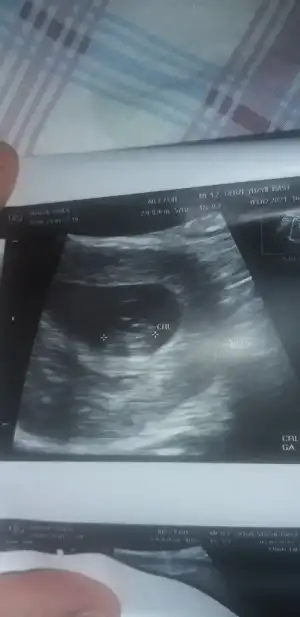

Bana da yapabılır mısınMaşallah çok tatlı bir bebişcanım ben ramzi teorisine göre bakıyorum eğer ki 6-8. Haftalar arasında ultrason görüntüsü varsa ordan plasenta konumuna göre bir yorum yapabilirim

Sen de mi yaa tühMaşallah canım ne kadar tatlı bir bebiş bu yaaBüyükken pek anlamıyorum ama banada sanki erkekmiş gibi geldi

Bana kız gibi geldi canımTeşekkür ederiz canım benim hemen atıyorum 7+5Eki Görüntüle 2791786 Eki Görüntüle 2791786

Yaa bana bakma sen ben bebek büyükken sadece hislerimle yorumluyorumSen de mi yaa tühhepimiz erkek gördük